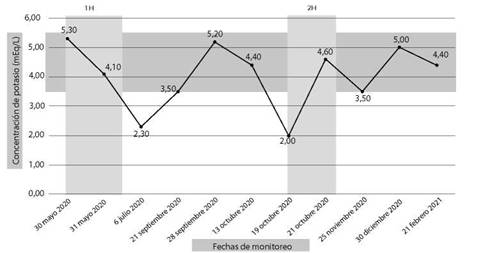

Cuatro meses después del cuadro inicial, el paciente fue hospitalizado nuevamente por cuadro de 4 horas de evolución caracterizado por presentar parálisis flácida de miembros superiores e inferiores, acompañado por parestesias en miembros inferiores, mialgias y disnea, sin alteración de funciones superiores, al examen físico con presión arterial 110/70, frecuencia cardíaca 90 latidos por minuto, tiroides de tamaño normal, sin alteraciones cardiopulmonares, sin temblor distal en manos. Entre los estudios de laboratorios realizados en emergencias destacó la presencia de hipopotasemia severa de 2,0 mEq/l. Con la sospecha de PPHT, se solicitó estudios de función tiroidea con resultados de TSH 0,01 uUI/ml (rango de referencia 0,4 y 4,5), T4 libre 3,09 ng/ dl (rango de referencia 0,8 y 1,65), anticuerpos anti TPO 552 UI/ml (rango de referencia 0 a 95) y anti tiroglobulina 211 UI/ml (rango de referencia 0 a 30), tiroglobulina 17 ng/ml (rango de referencia 0 a 55), ecografía tiroidea que reportó de tamaño y morfología normal, sin evidencia de lesiones nodulares (Figura 1), electrocardiograma sin alteraciones (Figura 2). Se inició tratamiento con fármacos antitiroideos y betabloqueadores, además de jarabe de potasio, el mismo que se disminuyó de forma gradual hasta su suspensión. Hasta la fecha el paciente mantiene tratamiento con tiamazol 20 mg por día, con control adecuado de la función tiroidea, sin nuevos episodios de debilidad y/o hipopotasemia. Se presenta la evolución de la concentración de potasio sérico en el Figura 3.

1H: primera hospitalización. 2 H: segunda hospitalización. Rango de referencia de potasio sérico: 3.5-5.5 mEq/l.

Fuente: Elaboración propia.

Figura 3. El rango de referencia de la concentración sérica de potasio es la banda horizontal gris. Mientras que la línea marca las fluctuaciones del potasio sérico.

Se considera que la PPHT se debe en general a la hipopotasemia producida por el incremento de la activación de la ATPasa sodio/potasio a nivel muscular, que ocurre como consecuencia del hipertiroidismo y que podría potenciarse con el ejercicio o el consumo alto en carbohidratos13,15, sin embargo, se han reportado casos de parálisis tirotóxica que cursan con normopotasemia16, cuya fisiopatología aún no está bien definida, pero que podrían corresponder a la periodicidad del propio cuadro, como en el caso presentado (Figura 3).